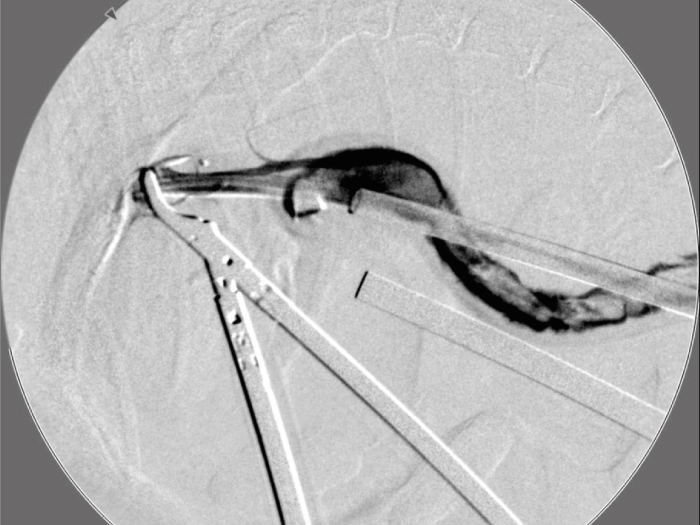

胆嚢の通路がちゃんと開通しているのか調べるために造影検査をしています。

この処置をすることで洗浄の効果と詰まりを確認することができます。

詰まりがないかを透視で確認しています。